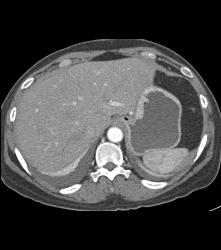

Antral Carcinoma With Peritoneal Tumor Implants